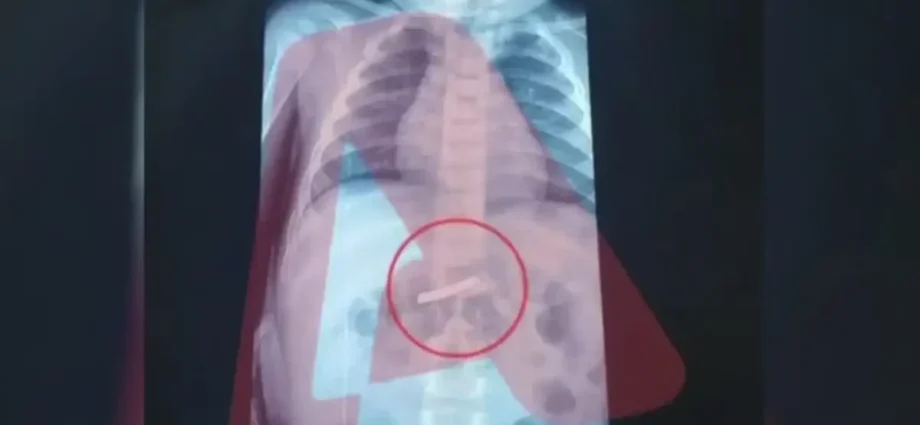

Ένας 3χρονος μεταφέρθηκε εσπευσμένα στο νοσοκομείο, το οποίο κατάπιε ένα ξυραφάκι. Το παιδί αφού έφτασε σε Παίδων της Αθήνας, υποβλήθηκε άμεσα σε ακτινογραφία, η οποία έδειξε ότι όντως υπήρχε το αιχμηρό αντικείμενο στο στομάχι του.

Όπως ενημέρωσαν οι γιατροί, τους γονείς του παιδιού, μετά την ακτινογραφία προσδιορίστηκε και το ακριβές σημείο όπου βρέθηκε το ξυραφάκι, ώστε οι χειρουργοί να προχωρήσουν σε επέμβαση αφαίρεσής του με ασφάλεια.